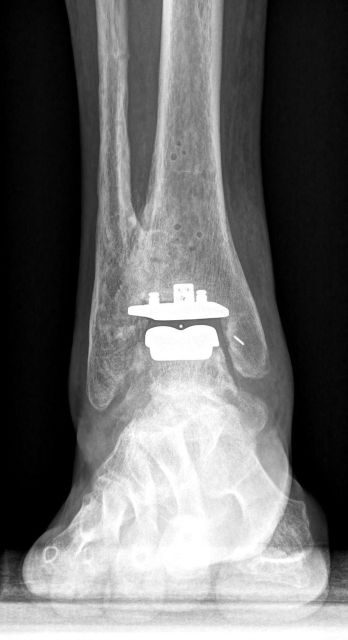

Bei eine Totalendoprothese des Sprunggelenks wird die verschlissene Oberfläche der Knochen mittels Implantaten ersetzt.

Die Verankerung im Knochen erfolgt zementfrei. Der körpereigene Knochen wächst nach einigen Wochen in die Oberflächenstruktur der Prothese ein, sodaß diese mit dem Knochen fix verankert ist. Die eigenen biologischen Bänder des Sprunggelenks bleiben dabei erhalten. Die Operation dauert in erfahrener Hand ca. 2 Stunden. Bis zur Abheilung der Hautwunde sollte nur eine geringe Belastung des Fußes erfolgen. Dabei wird eine Unterschenkelschiene zur Stabilisierung verwendet. Je nach Kraft und Geschicklichkeit benötigt man aus Sicherheitsgründen zwischen 2 und 6 Wochen Krücken zum Gehen. Aufgrund der komplexen Anatomie des Fußes und der häufigen Begleitpathologien sind häufig gleichzeitig noch andere Korrekturen am Fuß notwendig. Ein gleichzeitig bestehender Achsfehler des Fußes wird im Rahmen der Prothesenimplantation mitkorrigiert.

OSG-TP vorher-nachher